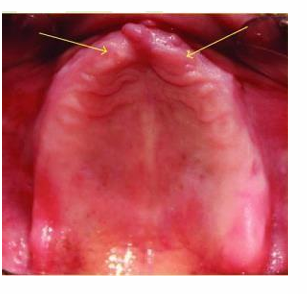

MFD EXAMS /23 6 1234567891011121314151617181920212223 You have 30 min to complete this exam. The timer will start once you begin Attention: Only a few minutes left! Please submit your answers soon. MFD 1 Get a quick sneak peek before the real exam !This trial quiz is designed to show you the question style, difficulty level, and how the options will appear on the platform. 1 / 23 1. What is the lethal dose and toxic dose of fluoride, management? Check 2 / 23 2. What the advantage of silver diamine over other methods and disadvantages ? Check 3 / 23 3. Method of topical fluoride application with concentration ? Check 4 / 23 4. What will happen if left untreated? Check 5 / 23 5. What changes that will happen if the habit stopped? Check 6 / 23 6. Give 3 of your initial stage of treatment? Check 7 / 23 7. What are the causes? Check 8 / 23 8. What is this? Check 9 / 23 9. Then they specified the type of pain and asked about the diagnosis Check 10 / 23 10. What other tests to check vitality of the pulp? Check 11 / 23 11. What are the factors will govern the Rx of Posterior cross bite ? Check 12 / 23 12. What are the factors that govern the treatment of anterior cross bite? Check 13 / 23 13. Name the appliance that you can use to treat this case? Check 14 / 23 14. Name 3 causes? Check 15 / 23 15. Name the most important clinical diagnostic information you need to know. (check RCSI intensive course )? Check 16 / 23 16. What do you see? Check 17 / 23 17. What is your treatment? Check 18 / 23 18. Name the investigations needed? Check 19 / 23 19. causes for gingival enlargement ? Check 20 / 23 20. What is the common side effect of this drug? Check 21 / 23 21. Name the drug that he may take to treat this condition? Check 22 / 23 22. The patient may have what? Check 23 / 23 23. What is this clinical condition? Check /31 2 12345678910111213141516171819202122232425262728293031 You have 30 min to complete this exam. The timer will start once you begin Attention: Only a few minutes left! Please submit your answers soon. MFD 2 Get a quick sneak peek before the real exam !This trial quiz is designed to show you the question style, difficulty level, and how the options will appear on the platform. 1 / 31 1. Mention 2 fixed space maintainers and 2 removable space maintainers other from mentioned : Check 2 / 31 2. Other space maintenance used for child lost primary second molar E before the eruption of the permanent molars ? Check 3 / 31 3. What are the difference between nance appliance and Transpalatal arch Check 4 / 31 4. What material used to attach band? Check 5 / 31 5. What instruction you give to patient? Check 6 / 31 6. Name other fixed space maintainer used in upper jaw and mechanism of their action? Check 7 / 31 7. What component of this appliance? Check 8 / 31 8. What is this appliance , for what its used ? Check 9 / 31 9. Treatment? Check 10 / 31 10. Define Abrasion and Erosion? Check 11 / 31 11. What does this picture show? Check 12 / 31 12. what investigations you can do ? Check 13 / 31 13. Drugs can lead to lichenoid reaction Check 14 / 31 14. What extra oral features in “ Lichenoid reaction )? Check 15 / 31 15. What microscopical features of it ( licheonoid reaction )? Check 16 / 31 16. Definitive diagnosis ? Check 17 / 31 17. Mention type of suggested biopsy ? Check 18 / 31 18. Mention 4 differential diagnosis ? Check 19 / 31 19. Mention 4 questions you will ask the patient ? Check 20 / 31 20. Give 4 intraoral decription of what you see ? Check 21 / 31 21. What the other surgery can be performed to make prothesis? Check 22 / 31 22. Can this tooth stand with fixed prothesis? (in the opg )à taken from Malek file ? Check 23 / 31 23. Radiograph of missing multiple teeth consider it according to Antes law? ON which tooth you will make Abutment ? Check 24 / 31 24. What is Antes law? Check 25 / 31 25. What is best one to use as abutment in fixed prosthesis A or B? Check 26 / 31 26. What relevance of this picture? Check 27 / 31 27. What’s complication of doing surgery in this area floor of mouth? Check 28 / 31 28. Other 2 radiograph needed in diagnosis? Check 29 / 31 29. Give 4 differential diagnosis? Check 30 / 31 30. What can you see ? Check 31 / 31 31. What is the name of radiograph? Check Your score is /30 1 123456789101112131415161718192021222324252627282930 You have 30 min to complete this exam. The timer will start once you begin Attention: Only a few minutes left! Please submit your answers soon. MFD 3 Get a quick sneak peek before the real exam !This trial quiz is designed to show you the question style, difficulty level, and how the options will appear on the platform. 1 / 30 1. Treatment? Check 2 / 30 2. Histopathology? Check 3 / 30 3. Differential diagnosis Check 4 / 30 4. Clinical features’? Check 5 / 30 5. Patient said, this lesion is very frequent, why? Check 6 / 30 6. What are the causes for ulcers? Check 7 / 30 7. Patient have other signs like uveitis ,Genital ulcerations which syndrome he had ? Check 8 / 30 8. Name of the lesion ? Check 9 / 30 9. Mention some TMJ movement ? Check 10 / 30 10. Blood supply ? Check 11 / 30 11. Nerve supply ? Check 12 / 30 12. Which muscles close? Check 13 / 30 13. Action of open and open wide? Check 14 / 30 14. Why it’s Atypical joint ? Check 15 / 30 15. Name of the ligaments ? Check 16 / 30 16. What would be your management? Check 17 / 30 17. Bacteria involved Check 18 / 30 18. Which type of Periodontitis? Check 19 / 30 19. Treatment? Check 20 / 30 20. Histopathology? Check 21 / 30 21. Differential diagnosis? Check 22 / 30 22. Clinical features? Check 23 / 30 23. What are the time frames for making a complaint? Check 24 / 30 24. What are the 3 points related to negligence? Check 25 / 30 25. Who is allowed access to the patient records? Check 26 / 30 26. How to differentiate if it is upper or lower motor neuron lesion? Check 27 / 30 27. Management? Check 28 / 30 28. What are the causes? Check 29 / 30 29. What should you advise the patient to do? Check 30 / 30 30. What is this lesion? Check Your score is /24 1 123456789101112131415161718192021222324 You have 30 min to complete this exam. The timer will start once you begin Attention: Only a few minutes left! Please submit your answers soon. MFD 4 Get a quick sneak peek before the real exam !This trial quiz is designed to show you the question style, difficulty level, and how the options will appear on the platform. 1 / 24 1. What does MRONJ stands for? Check 2 / 24 2. Give definition for MRONJ Check 3 / 24 3. For what medical problems these medications are used? Check 4 / 24 4. Stages of MRONJ 3 Check 5 / 24 5. What’s this appliance? Check 6 / 24 6. At what age is it used? Check 7 / 24 7. What type of malocclusion is it used to treat? Check 8 / 24 8. What changes will produce? (4 options) Check 9 / 24 9. Disadvantages? Check 10 / 24 10. Why is it flabby tissue? Check 11 / 24 11. what is this condition called? Check 12 / 24 12. Causes ? Check 13 / 24 13. Clinical Features ? Check 14 / 24 14. How to avoid it ? Check 15 / 24 15. Management? Check 16 / 24 16. Ideal post length and width Check 17 / 24 17. Definition of Ferrule it’s the Check 18 / 24 18. What is the importance of the ferrule effect ? Check 19 / 24 19. Describe the radiolucency? Check 20 / 24 20. Give 6 differential diagnosis? Check 21 / 24 21. Give 5 radiographical features? Check 22 / 24 22. What is the difference between incisional and excisional biopsy? Check 23 / 24 23. What other 2 plain radiographs we can we can take? Check 24 / 24 24. ALARA? Check Your score is /22 1 12345678910111213141516171819202122 You have 30 min to complete this exam. The timer will start once you begin Attention: Only a few minutes left! Please submit your answers soon. MFD 5 Get a quick sneak peek before the real exam !This trial quiz is designed to show you the question style, difficulty level, and how the options will appear on the platform. 1 / 22 1. . Types of external root resorption? Check 2 / 22 2. The cause of root resorption in the pic? Check 3 / 22 3. How you will treat it? Check 4 / 22 4. What is this probe? Check 5 / 22 5. What is the mark a ? Check 6 / 22 6. What is the mark b ? Check 7 / 22 7. What is the score from the given reading? Check 8 / 22 8. What is the treatment need of the patient according to the score? Check 9 / 22 9. What is the differential diagnosis ? Check 10 / 22 10. Four clinical features of the lesion? Check 11 / 22 11. Treatment ? Check 12 / 22 12. Describe what do you see? Check 13 / 22 13. Causes for it ? Check 14 / 22 14. Treatment ? Check 15 / 22 15. Picture of patient with Anaphylaxis…after taking Check 16 / 22 16. What is diagnosis? - Check 17 / 22 17. What a the signs of Anaphyalxis reactions ? Check 18 / 22 18. What first line of treatment? Dose? Route of Adminstration? Check 19 / 22 19. Other drug used? Check 20 / 22 20. What are expected complications if not treated ? Check 21 / 22 21. What precautions should be made to prevent anaphylaxis reaction ? - Check 22 / 22 22. Name 10 drug in emergency used with their route of Administration and their condition they use in? Check Your score is /36 1 123456789101112131415161718192021222324252627282930313233343536 You have 30 min to complete this exam. The timer will start once you begin Attention: Only a few minutes left! Please submit your answers soon. MFD 6 Get a quick sneak peek before the real exam !This trial quiz is designed to show you the question style, difficulty level, and how the options will appear on the platform. 1 / 36 1. . What are cases that you have to extract the primary tooth? Check 2 / 36 2. D. What are the indications for extraction? Check 3 / 36 3. What are your treatment options? Check 4 / 36 4. Investigations? Check 5 / 36 5. Type of trauma? Check 6 / 36 6. Patient diagnosed with sjorgen syndrome Histology ? - Check 7 / 36 7. Patient diagnosed with sjorgen syndrome Mention four blood investigations ? Check 8 / 36 8. Patient diagnosed with sjorgen syndrome Mention two sites where can we take the biopsy Check 9 / 36 9. Patient diagnosed with sjorgen syndrome How can you differentiate between primary and secondary ? Check 10 / 36 10. Gingival inflammation present in which syndrome Check 11 / 36 11. What is the treatment? Check 12 / 36 12. mention another connective tissue disease that can lead to lesions “ intraorally “ similar to the Lichen planus ? Check 13 / 36 13. what serious complication can arise from Erosive lichen planus ? Check 14 / 36 14. If it was atrophic lesion what histology might be seen ? Check 15 / 36 15. List the histological features of lichen planus ? Check 16 / 36 16. Lichen planus what dose it affect? Check 17 / 36 17. Age group commonly affected ? -ref SAQ Check 18 / 36 18. What are the clinical presentation ‘ types of lichen planus ‘ Check 19 / 36 19. What might you see in patient’s body that has a relation to this lesion? Check 20 / 36 20. What are the differential diagnoses? Check 21 / 36 21. Factors for platelet adhesion? Check 22 / 36 22. What can you see? Check 23 / 36 23. Other 2 process of hemostasis? Check 24 / 36 24. Two diseases in which they increase ? Check 25 / 36 25. Two diseases in which they decrease? Check 26 / 36 26. Medical term when they decrease? And if they increased Check 27 / 36 27. Function Check 28 / 36 28. Life span ? Check 29 / 36 29. From where they arise? Check 30 / 36 30. Normal number? Check 31 / 36 31. What are the function of the guiding plane ? Check 32 / 36 32. The success rate ? Check 33 / 36 33. Mention single extra preparation requirement for Resin bonded bridge in posterior teeth ? Check 34 / 36 34. Mention 5 preparation features of it? Check 35 / 36 35. Give two advantages of it ? Check 36 / 36 36. What’s the name of this prosthesis? Check Your score is /23 1 1234567891011121314151617181920212223 You have 30 min to complete this exam. The timer will start once you begin Attention: Only a few minutes left! Please submit your answers soon. MFD 7 Get a quick sneak peek before the real exam !This trial quiz is designed to show you the question style, difficulty level, and how the options will appear on the platform. 1 / 23 1. If the same scenario but the tooth is subluxated. What is the management? Check 2 / 23 2. Aim of this procedure Check 3 / 23 3. Steps to do this procedure? Check 4 / 23 4. Management? How to asses the vitality of the tooth Check 5 / 23 5. Mention factors that can affect the treatment plan ? Check 6 / 23 6. Identify the Kenneyd’s classification Check 7 / 23 7. Name its parts? Check 8 / 23 8. Uses of Surveyor Check 9 / 23 9. What is this ? Check 10 / 23 10. Criteria for hand piece sterilization Check 11 / 23 11. steps for wrapped instrument sterilization process ( ref : sterilization in SDCEP)? Check 12 / 23 12. What is the difference between sterilization and decontamination? Check 13 / 23 13. Optimal temperature & pressure & time for autoclave? Check 14 / 23 14. Difference between vacuum and non-vacuum autoclave in mechanism? Check 15 / 23 15. Optimum temperature? Check 16 / 23 16. Advantage of vaccum over non vaccum? Check 17 / 23 17. What is the significance of forehead wrinkling? Check 18 / 23 18. What is Ramsy haunt syndrome ? Rx ? and is it LMN or UMN ? Check 19 / 23 19. Enumerate 3 extracranial and intracranial causes for this ? Check 20 / 23 20. What are the branches of facial nerve? Check 21 / 23 21. Why do we suture the eye in a patient with Facial Palsy? Check 22 / 23 22. Differentiate between Upper and Lower Motor Neuron lesions? Check 23 / 23 23. What is shown in photograph? Check Your score is /27 0 123456789101112131415161718192021222324252627 You have 30 min to complete this exam. The timer will start once you begin Attention: Only a few minutes left! Please submit your answers soon. MFD 8 Get a quick sneak peek before the real exam !This trial quiz is designed to show you the question style, difficulty level, and how the options will appear on the platform. 1 / 27 1. Mention 4 diseases you would see in HIV Patients? Check 2 / 27 2. Give 2 differential diagnosis for this lesion? Check 3 / 27 3. Describe the lesion shown in Photograph B? Check 4 / 27 4. What is your diagnosis ? Check 5 / 27 5. Describe the lesion shown in Photograph A? Check 6 / 27 6. Disadvantages of gold ? Check 7 / 27 7. Ideal cement for All Porcelain? Check 8 / 27 8. Which cement would u use for high caries risk patient? Check 9 / 27 9. How much would you prepare for functional and non-functional cusps in Gold Crown? Check 10 / 27 10. what crown would you go for in bruxism patients out of these 3? Check 11 / 27 11. Name the 3 restorations? Check 12 / 27 12. After administering Local Anesthesia and deciding the choice of biopsy. What should be done before biopsying the lesion? Check 13 / 27 13. Name 2 systemic steroids with dosage you would recommend for this patient? Check 14 / 27 14. Name 2 topical steroids with dosage you would recommend for this patient? Check 15 / 27 15. What is your diagnosis? Check 16 / 27 16. Describe the lesion shown in photograph? Check 17 / 27 17. Name 5 options to increase retention and stability in class l Check 18 / 27 18. E. What is the function of the RPI system ? Check 19 / 27 19. What are the 2 disadvantages of the 2 restorations you mentioned? Check 20 / 27 20. What materials are your 2 restorations made of? Check 21 / 27 21. Other than implants what restoration would you place in this patient? Check 22 / 27 22. Which Kennedy’s classification is this? Check 23 / 27 23. Describe your management? Check 24 / 27 24. What may be the patient complaint? Check 25 / 27 25. What are the causes of this? Check 26 / 27 26. Describe what you see in the photograph? Check 27 / 27 27. which 4 examinations would you undertake? Check Your score is /31 0 12345678910111213141516171819202122232425262728293031 You have 30 min to complete this exam. The timer will start once you begin Attention: Only a few minutes left! Please submit your answers soon. MFD 9 Get a quick sneak peek before the real exam !This trial quiz is designed to show you the question style, difficulty level, and how the options will appear on the platform. 1 / 31 1. Describe what you see in the photograph? Check 2 / 31 2. Three other features of this syndrome ? Check 3 / 31 3. What is the medical condition associated with it “? Multiple OKC? Check 4 / 31 4. Where expansion occurs in the OKC ? Check 5 / 31 5. From which cells this lesion arises from? Check 6 / 31 6. What is your diagnosis? Check 7 / 31 7. What is the histopathology of the lesion shown in Histology slide? Check 8 / 31 8. Give 4 differential diagnosis? Check 9 / 31 9. What is the consequence of premature loss of deciduous teeth? Check 10 / 31 10. Identify those appliances and mention one use for each and mode of action? Check 11 / 31 11. What component of appliance no. 3 ? Check 12 / 31 12. How to overcome open bite disadvantage ? Check 13 / 31 13. What are Disadvantages of this appliance ? Check 14 / 31 14. What Ceph changes are expected while using this appliance ? Check 15 / 31 15. What is the construction of Twin Block Appliance? Check 16 / 31 16. What skeletal and dental changes are expected while using this appliance ? Check 17 / 31 17. What is the ideal age to treat this condition >? Check 18 / 31 18. Indications of the Twin Block Appliance? Two Check 19 / 31 19. Name the Appliance used to correct this? Check 20 / 31 20. What is the treatment? Check 21 / 31 21. How to prevent it Check 22 / 31 22. Mention three mechanisms of action of Fluoride? Check 23 / 31 23. What is the disease caused by excess Fluoride? Check 24 / 31 24. What are the risk factors associated with this patient? Check 25 / 31 25. Name the principal organism causing this? Check 26 / 31 26. what are the principles of the access cavity Check 27 / 31 27. What is your diagnosis? Check 28 / 31 28. What are principles of cavity preparation? Check 29 / 31 29. What is your Periapical diagnosis? Check 30 / 31 30. What is your Pulpal diagnosis? Check 31 / 31 31. Which test would you undertake? Check Your score is /21 0 123456789101112131415161718192021 You have 30 min to complete this exam. The timer will start once you begin Attention: Only a few minutes left! Please submit your answers soon. MFD 10 Get a quick sneak peek before the real exam !This trial quiz is designed to show you the question style, difficulty level, and how the options will appear on the platform. 1 / 21 1. Patient is 20 years old Mention two treatment options for this case ? Check 2 / 21 2. Patient is 20 years old What is the long term risk for not treating this case ? Check 3 / 21 3. Name of this appliance in the next picture? Check 4 / 21 4. What is the wire used ? Check 5 / 21 5. For which orthodontic cases this appliance is necessary ? Check 6 / 21 6. Why we use retainer ? Check 7 / 21 7. Describe what you see ? Check 8 / 21 8. Differential diagnosis:- Check 9 / 21 9. Name of those muscles ? Check 10 / 21 10. Name the Extrinsic muscles of the tongue? Check 11 / 21 11. . Which nerves innervate the Extrinsic muscles of the tongue?. Check 12 / 21 12. What is the somatic innervation of anterior 2/3 of tongue? Check 13 / 21 13. Which nerve supplies the posterior 1/3 of tongue?. Check 14 / 21 14. From which Pharyngeal arch posterior 1/3 derived from? Check 15 / 21 15. Mention the intrinsic muscle of the tongue ? Check 16 / 21 16. What is the name of this condition ? name the lesion on the skin ? Check 17 / 21 17. Mention 3 drugs that causing it ? Check 18 / 21 18. 2 infections associated with it Check 19 / 21 19. Mention 2 immediate treatment ? Check 20 / 21 20. Why this condition can be fatal ? Check 21 / 21 21. Which test would you undertake? Check Your score is